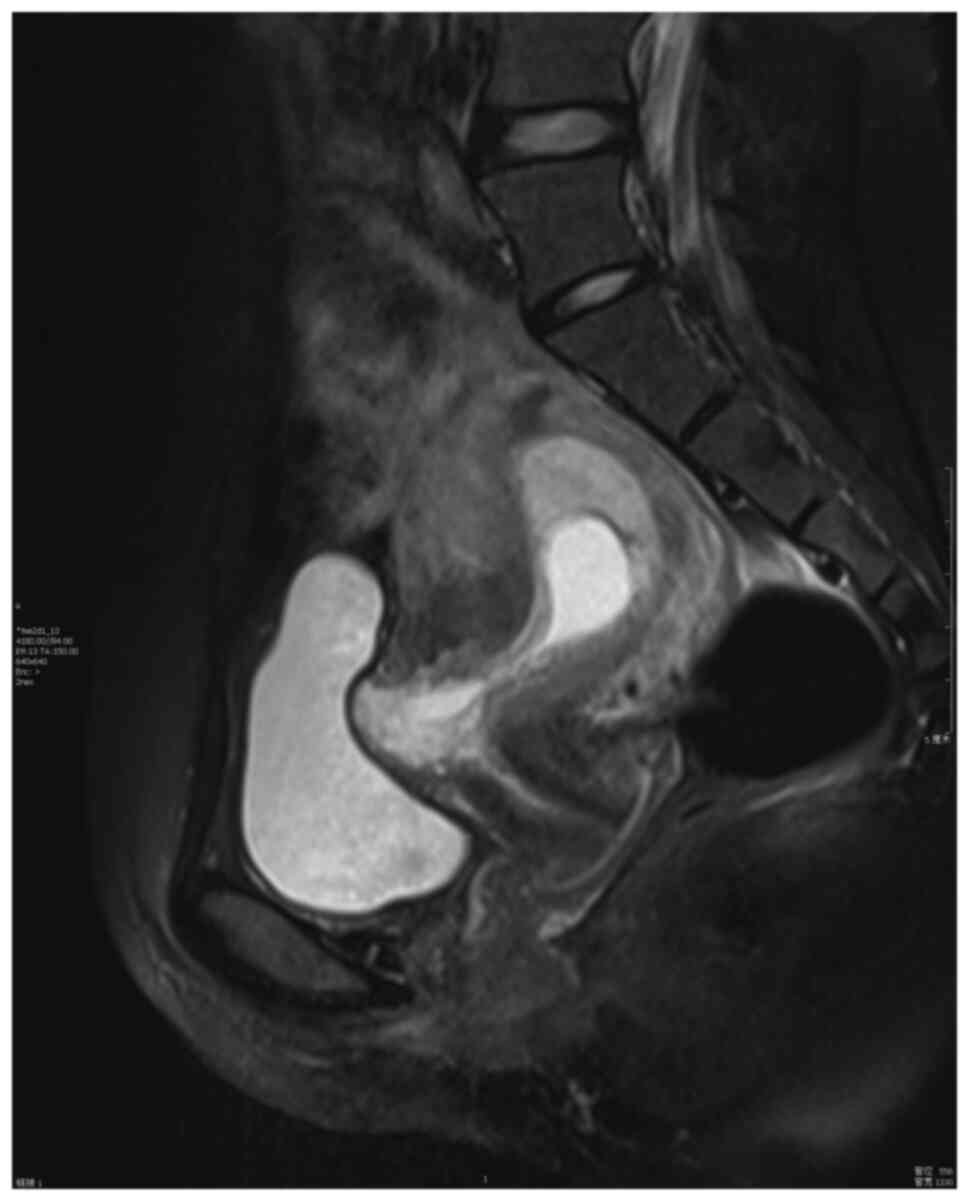

The surgical procedure was as follows: Laparoscopy was performed under general anesthesia in the supine lithotomy position. Laparoscopy displayed a bulging in the lower uterine segment (Fig. 1). Subsequently, a 12 IU vasopressin solution was injected into the uterus. The bladder peritoneum was incised to expose the pregnancy scar; a bulging was noted comprised of blood vessels and gestational tissues. The gestational tissue was rapidly removed with grasping forceps, scissors and an aspirator (Figs. 2 and 3). This procedure was performed as quickly as possible. The myometrial scar was resected and stanched by bipolar coagulation. Finaly, a continuous suture with an absorbable suture (1-0) was used to close the uterine wound (Fig. 4).

Figure 1

Image illustrating a bulging in the lower uterine segment following laparoscopy and the positioning of the gestational sac convex to the bladder (patient 5).

The imaging criteria for diagnosis (Figs. 5 and 6; patient 5) include the following: An empty uterus and cervical canal; the development of the GS toward the anterior wall of the isthmic portion; the loss of myometrial anterior wall continuity on a sagittal plane of the uterus through the GS; the absence of or diminished healthy myometrium between the bladder and the sac; the monitoring of peri-trophoblastic vascular flow with high velocity and low impedance surrounded by the sac using Doppler examination (10,11). The pathological features included trophoblast invasion and destructive growth to the uterine wall. Since the opened blood vessels do not possess systolic function and the scar tissue cannot contract, a potential misdiagnosis leading to an artificial or spontaneous abortion will result in massive hemorrhage (12).

Figure 5

Magnetic resonance imaging of the empty uterus, the empty cervical canal, and the cesarean scar pregnancy (patient 5).

Figure 6

Magnetic resonance imaging of the GS surrounded by the myometrium and absence of the myometrium between the GS and the bladder. GS, gestational sac (patient 5).